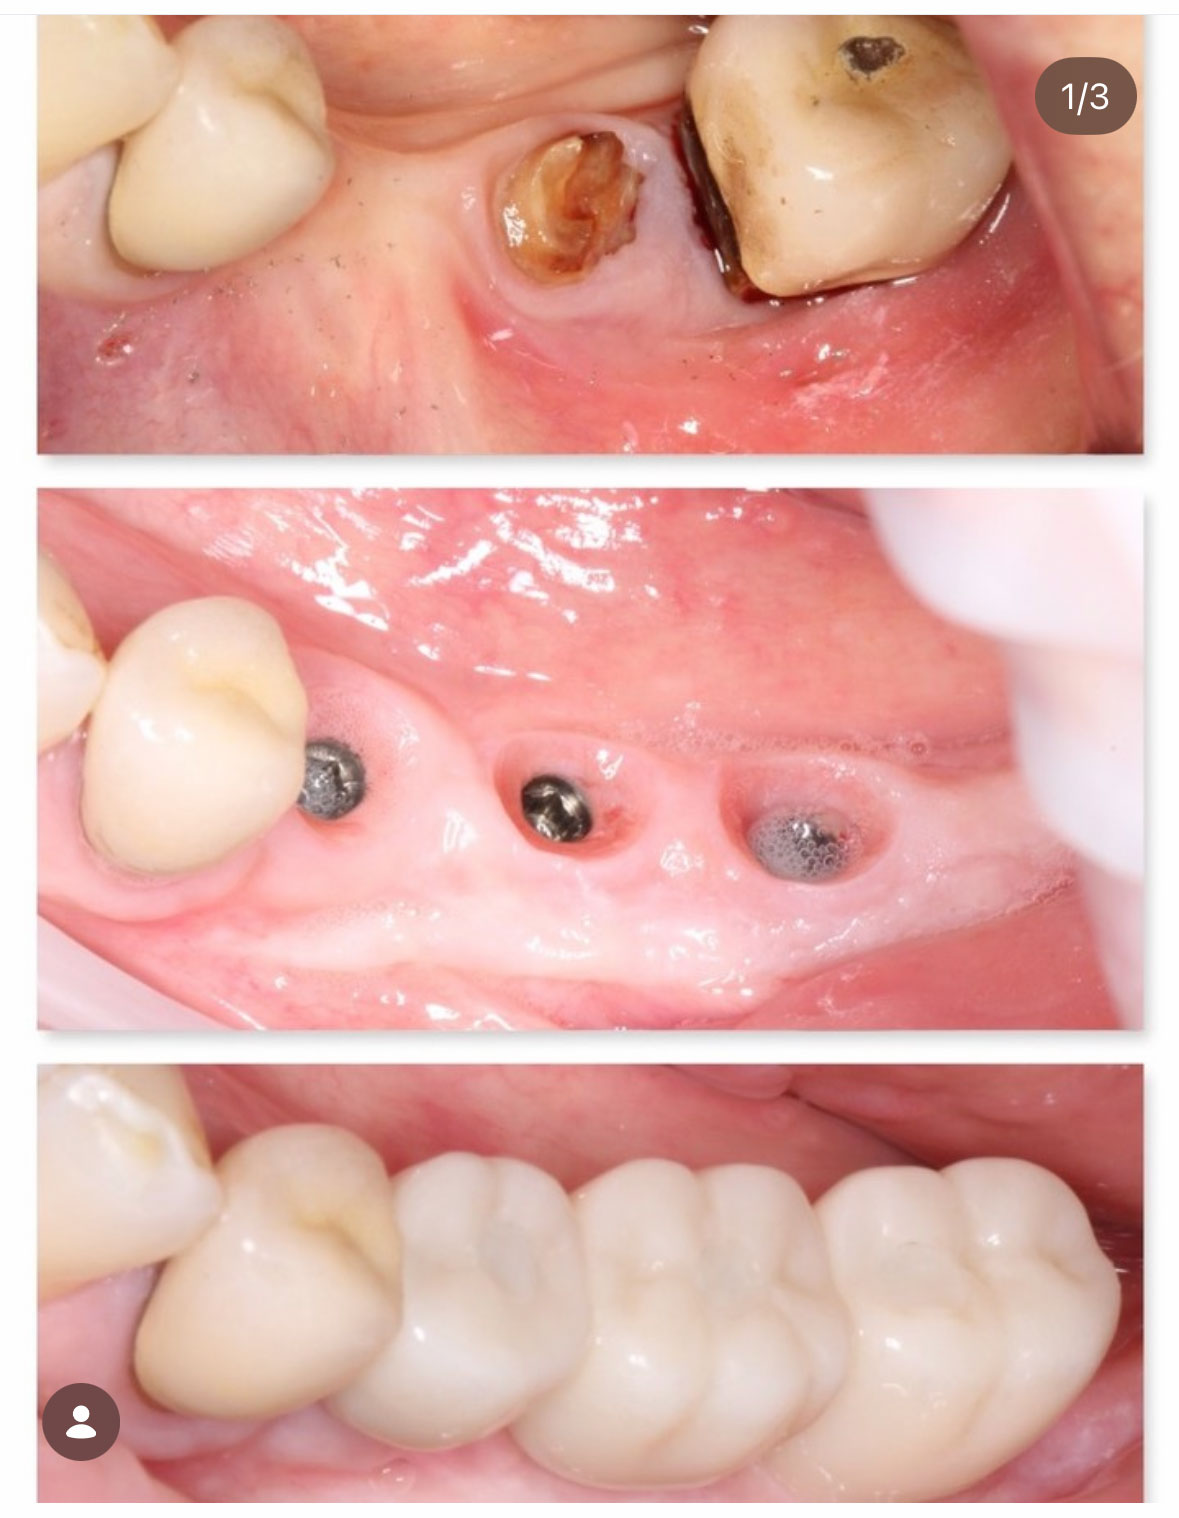

Before & Afters of Dental Implant Patients

Complete Dental Implant Cases Gallery

General Disclaimer: The results in the photographs are examples only and do not imply any certainty of the result of a procedure, and all outcomes are subject to the circumstances of the individual patient.